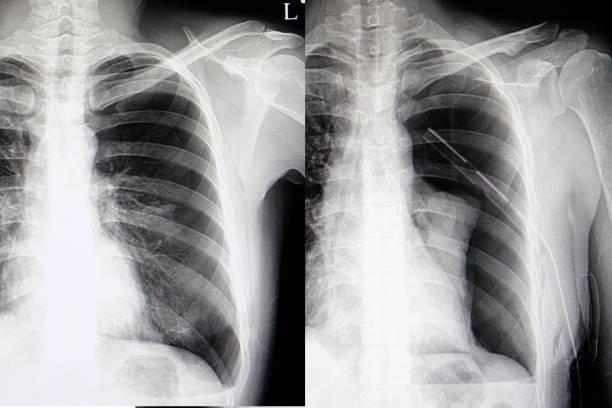

흉부 X선 검사

기흉이 의심되는 환자에게는 흉부 X선 검사를 실시하여 기흉이 있는지 확인할 수 있습니다. 이 방법은 비교적 쉽고 빠르게 기흉을 진단할 수 있습니다.

CT 스캔 검사

CT 스캔 검사는 폐의 3D 영상을 생성하여 누출된 공기가 있는 위치와 기흉의 원인을 파악할 수 있습니다.